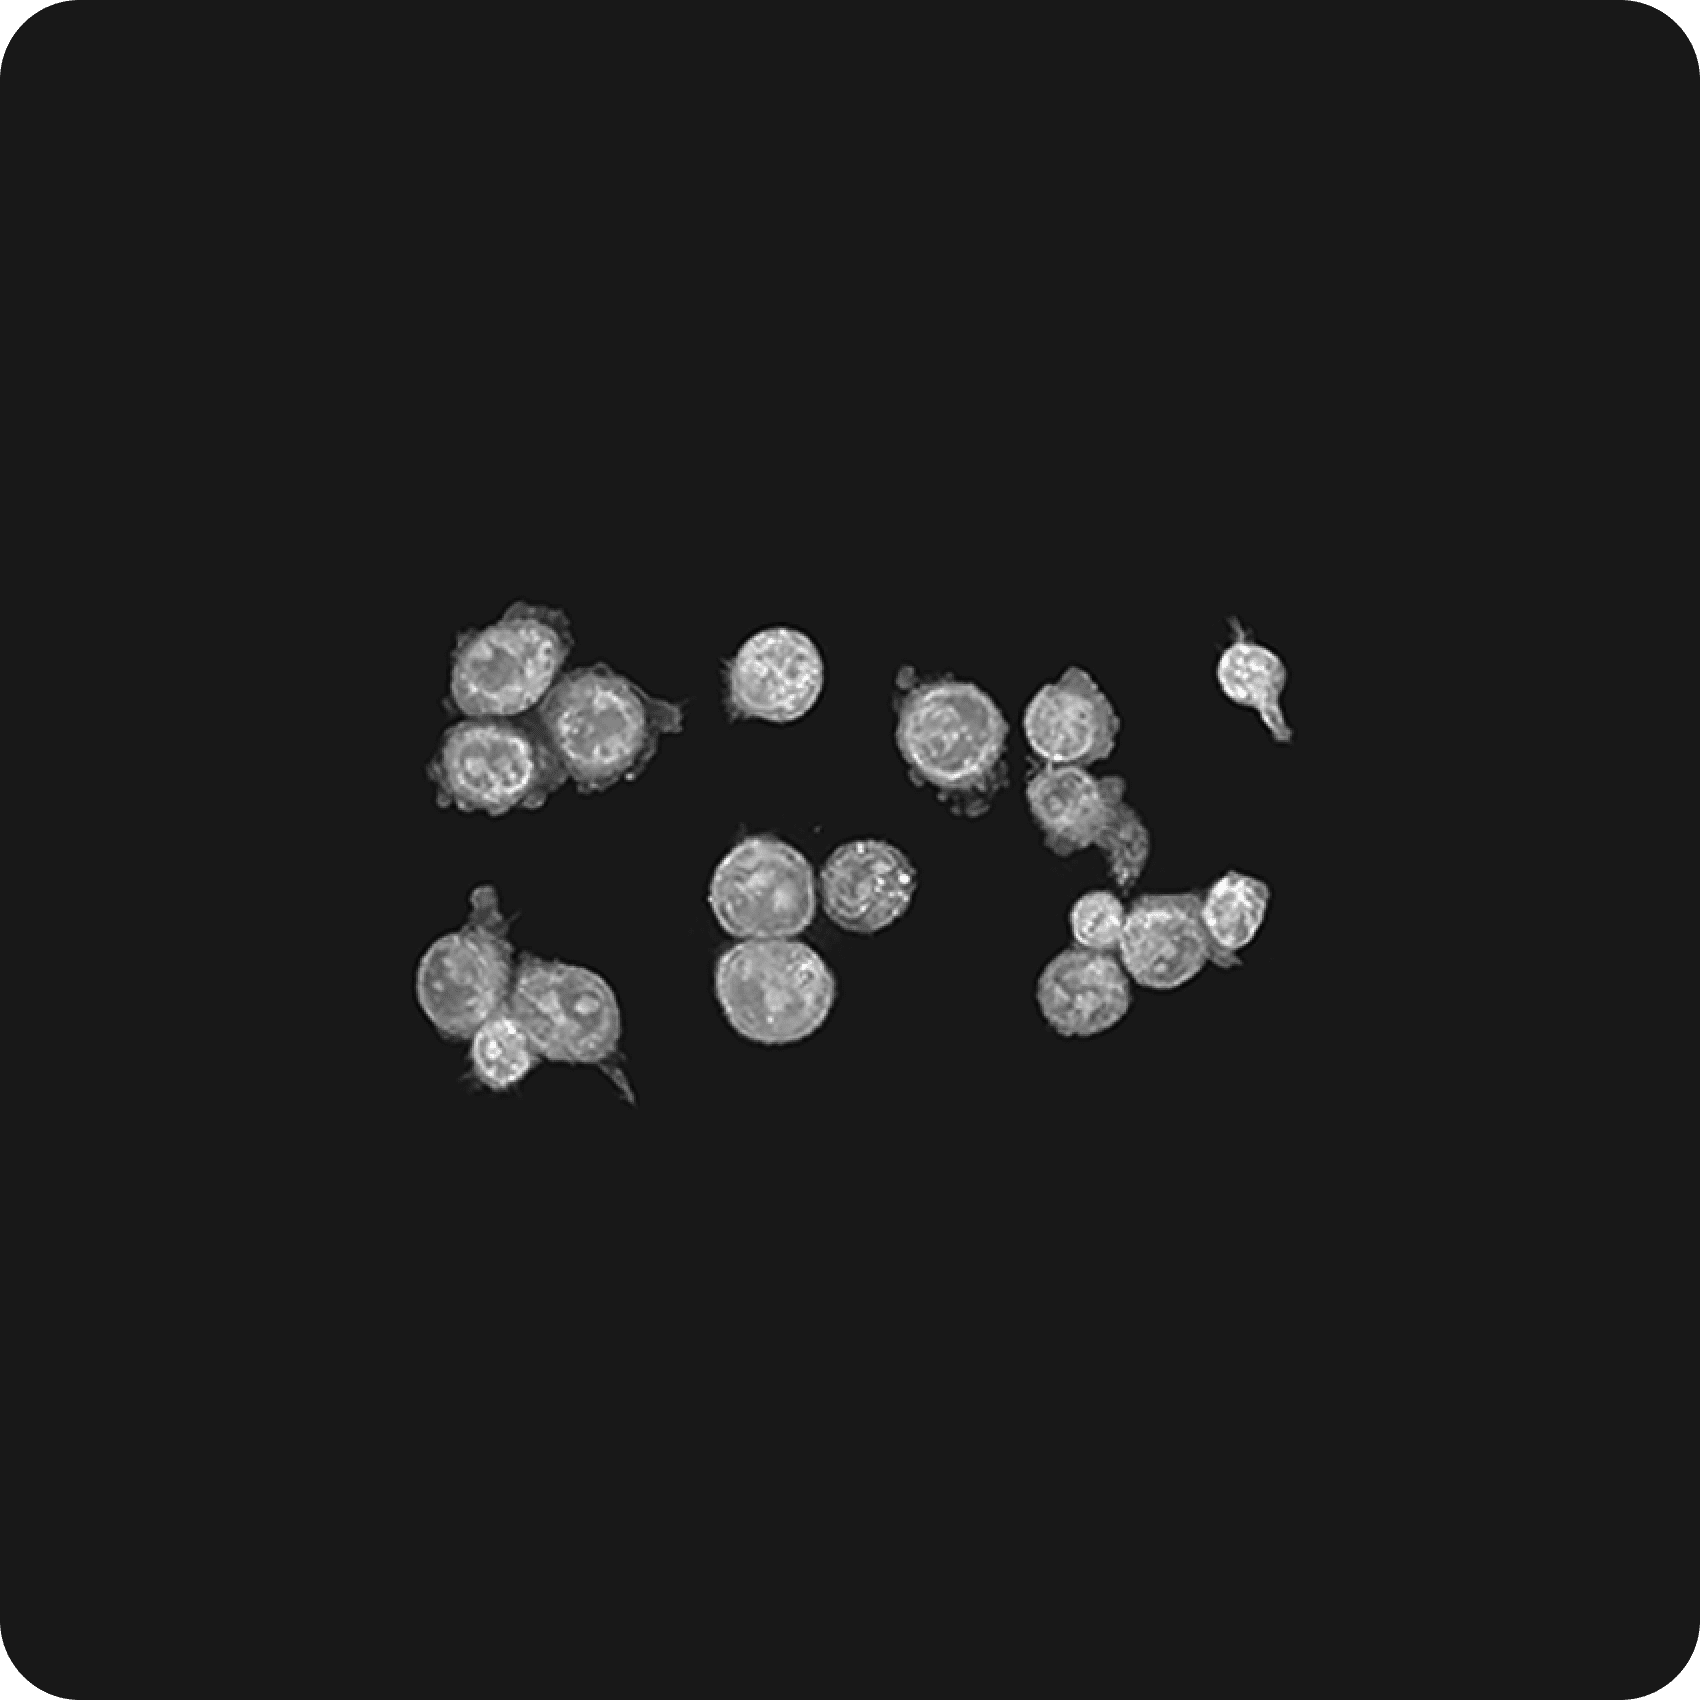

- 3D 생물학 (오가노이드/스페로이드): 오가노이드, 스페로이드, 미세 유체 장치 등 복잡한 3D 배양 세포 및 조직을 이해하는 데 필수적이며, 살아있는 3D 샘플의 비표지, 고해상도, 실시간 시각화 및 장기 종단 연구를 가능하게 합니다.

토모큐브는 홀로토모그래피와 관련된 모든 이론, 광학, 하드웨어, 소프트웨어, AI 기술들을 자체적으로 개발하고 있으며 이를 통해 글로벌 시장에서 초격차를 유지하고 있습니다. 박용근 토모큐브 대표이사는 "토모큐브는 홀로토모그래피 기술로 세계에서 가장 앞서 있으며 경쟁사 대비 5년 이상의 기술 초격차를 유지 중"이라며 "오가노이드와 같은 3차원 샘플을 찍을 수 있는 기술력을 보유한 회사는 토모큐브가 유일하다"고 설명합니다. 경쟁사의 나노라이브 현미경은 내부가 복잡하고 측정 단계가 여러 단계로 직관적이지 않으며, 특히 두꺼운 오가노이드 촬영이 어렵다는 단점이 있습니다. 반면 토모큐브의 2세대 기술은 LED 광원을 사용하여 세포의 절단 없이 두꺼운 오가노이드를 실시간으로 관찰 할 수 있습니다. 제품의 수익률이 50%에 육박한다는 것은 시장의 독점적인 공급자를 나타내는 중요한 지표입입니다. 토모큐브는 또 하나의 패러다임을 창조한 시장의 지배자이자 파괴자입니다.